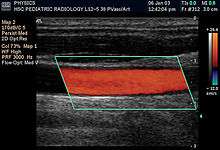

Doppler ultrasonography is used to study blood flow and muscle motion. The different detected speeds are represented in color for ease of interpretation, for example leaky heart valves: the leak shows up as a flash of unique color. Colors may alternatively be used to represent the amplitudes of the received echoes.

- Doppler mode: This mode makes use of the Doppler effect in measuring and visualizing blood flow

- Color Doppler: Velocity information is presented as a color-coded overlay on top of a B-mode image

Doppler ultrasonography

Sonography can be enhanced with Doppler measurements, which employ the Doppler effect to assess whether structures (usually blood)[16] are moving towards or away from the probe, and its relative velocity. By calculating the frequency shift of a particular sample volume, for example flow in an artery or a jet of blood flow over a heart valve, its speed and direction can be determined and visualised. This is particularly useful in cardiovascular studies (sonography of the vascular system and heart) and essential in many areas such as determining reverse blood flow in the liver vasculature in portal hypertension. The Doppler information is displayed graphically using spectral Doppler, or as an image using color Doppler (directional Doppler) or power Doppler (non directional Doppler). This Doppler shift falls in the audible range and is often presented audibly using stereo speakers: this produces a very distinctive, although synthetic, pulsating sound.

It should be noted here that there are no standards for the display of color Doppler. Some laboratories show arteries as red and veins as blue, as medical illustrators usually show them, even though some vessels may have portions flowing towards and portions flowing away from the transducer. This results in the illogical appearance of a vessel being partly a vein and partly an artery. Other laboratories use red to indicate flow toward the transducer and blue away from the transducer. Still other laboratories prefer to display the sonographic Doppler color map more in accord with the prior published physics with the red shift representing longer waves of echoes (scattered) from blood flowing away from the transducer; and with blue representing the shorter waves of echoes reflecting from blood flowing toward the transducer. Because of this confusion and lack of standards in the various laboratories, the sonographer must understand the underlying acoustic physics of color Doppler and the physiology of normal and abnormal blood flow in the human body (see Red shift[17][18][19]).